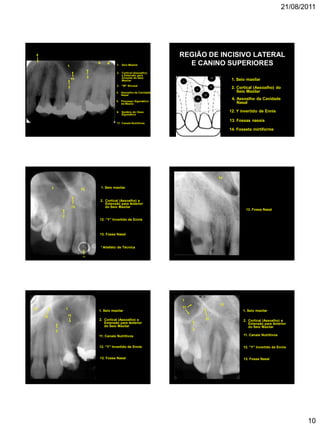

REGIÃO DE INCISIVO LATERAL

E CANINO SUPERIORES

14. Fosseta mirtiforme

13. Fossas nasais

1. Seio maxilar

12. Y invertido de Ennis

4

2

1

12

13

14

2. Cortical (Assoalho) do

Seio Maxilar

4. Assoalho da Cavidade

Nasal

131

13. Fossa Nasal

12. “Y” Invertido de Ennis

2. Cortical (Assoalho) e

Extensão para Anterior

do Seio Maxilar

*

* Artefato de Técnica

13 1

11. Canais Nutritivos

11